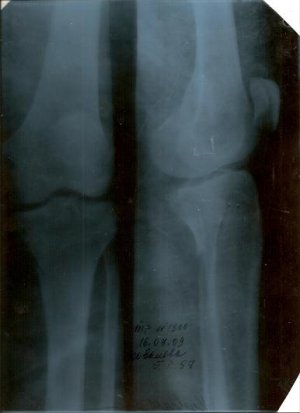

Б/берцовой кости левой голини .

15 июля наложили гипс нога не болела не зависимо как бы не вертела ею 15 августа самостоятельно сняли гипс и начала самостоятельно разрабатывать ногу , делать ванны с морской солю в теплой воде, втирать пихтоватое масло в перелом . 16 августа начала болеть нога 17.08.09 сделали снимок, а перелом как такой как был месяц тому назад совсем не зажил.